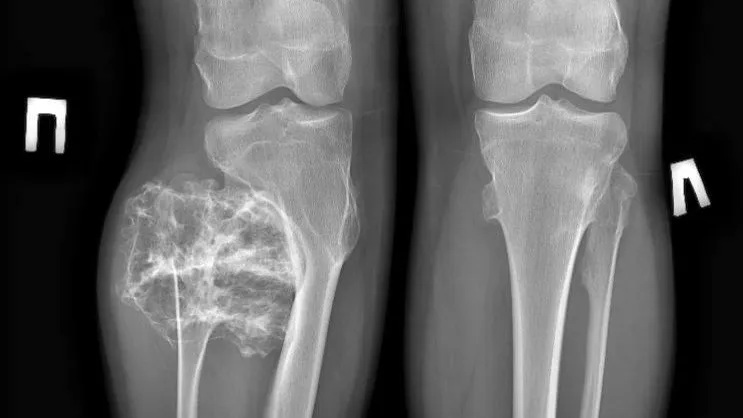

Специалисты Московской областной детской клинической травматолого-ортопедической больницы (МОДКТОБ) спасли 15-летнего подростка с огромным твердым новообразованием в области малоберцовой кости. Об этом сообщает Министерство здравоохранения Московской области.

Врачи выявили у него остеохондрому, которая представляет собой доброкачественное костное новообразование размером 9х8х8 см. Пациенту провели плановое хирургическое лечение.

По его словам, в рамках операции специалисты удалили образование в пределах здоровой костной ткани, функцию ноги удалось сохранить. После полученного лечения подростка выписали домой на амбулаторное лечение.